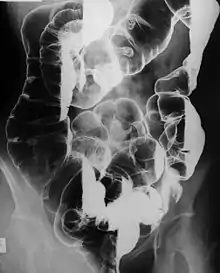

![]() صورة ميكروسكوبية لسليلة قولونية من نوع بوتز-جيغرز صورة ميكروسكوبية لسليلة قولونية من نوع بوتز-جيغرز | |

- تصوير الأمعاء الدقيقة بالأشعة كل عامين،